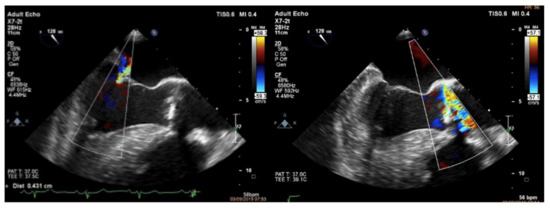

2. Case Report